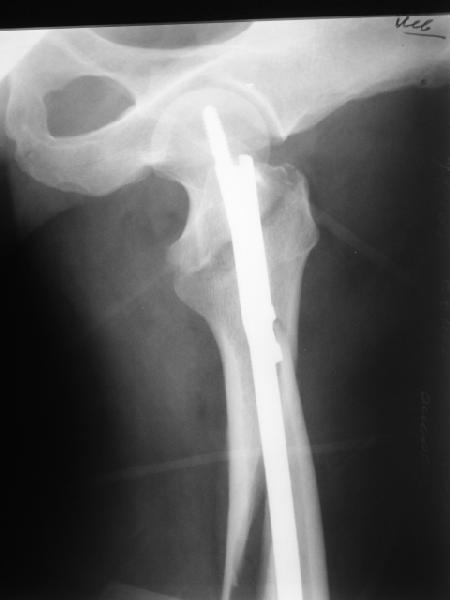

Как раз недавно у меня был примерный случай: больному 36 лет, поступил ночью, травма в результате мотоциклетной аварии, кроме чрезвертельного и спирального перелома левого бедра имеется переломы костей предплечья с этой же стороны. Скелетное вытяжение, а на следующий день больной про оперирован на ортопедическом столе с дистракцией. Чтобы не расколоть чрезвертельный перелом провели временную спицу ближе к переднему кортексу, из малого разреза костодержатель для репозиции, а фиксацию провели антиградным штифтом. Этапы операции на снимках.

Да, сейчас это и у нас самый напрашивающийся выбор. Сделали гвоздем ChM, картинки в приложении.

Второй случай тоже репозиция из малого доступа, больному 19 лет, множественные огнестрельные повреждениия конечностей, живота и черепа, правая конечность холодная, без пульсации. Ортопедический диагноз: огнестрельный перелом правого бедра. При срочной ангиографии повреждения сосудов не подтвердилось, конечность из-за ургентности состояния больного зафиксирована временным наружным фиксатором и больной оставлен на операционном столе для срочной лапаротомии хирургической службой.

Больной долго оставался нестабильным, только на 14 день удалось заменить на антеградный интромедуллярный штифт TFN (trochanteric femoral nail) SmithNephew. После неудачной попытки закрытой репозиции, несмотря на использование "joystick", проксимальный стержень от

наружного фиксатора, (перелом начал срастаться) репозицию провели из малого доступа, затем остальные этапы операции.